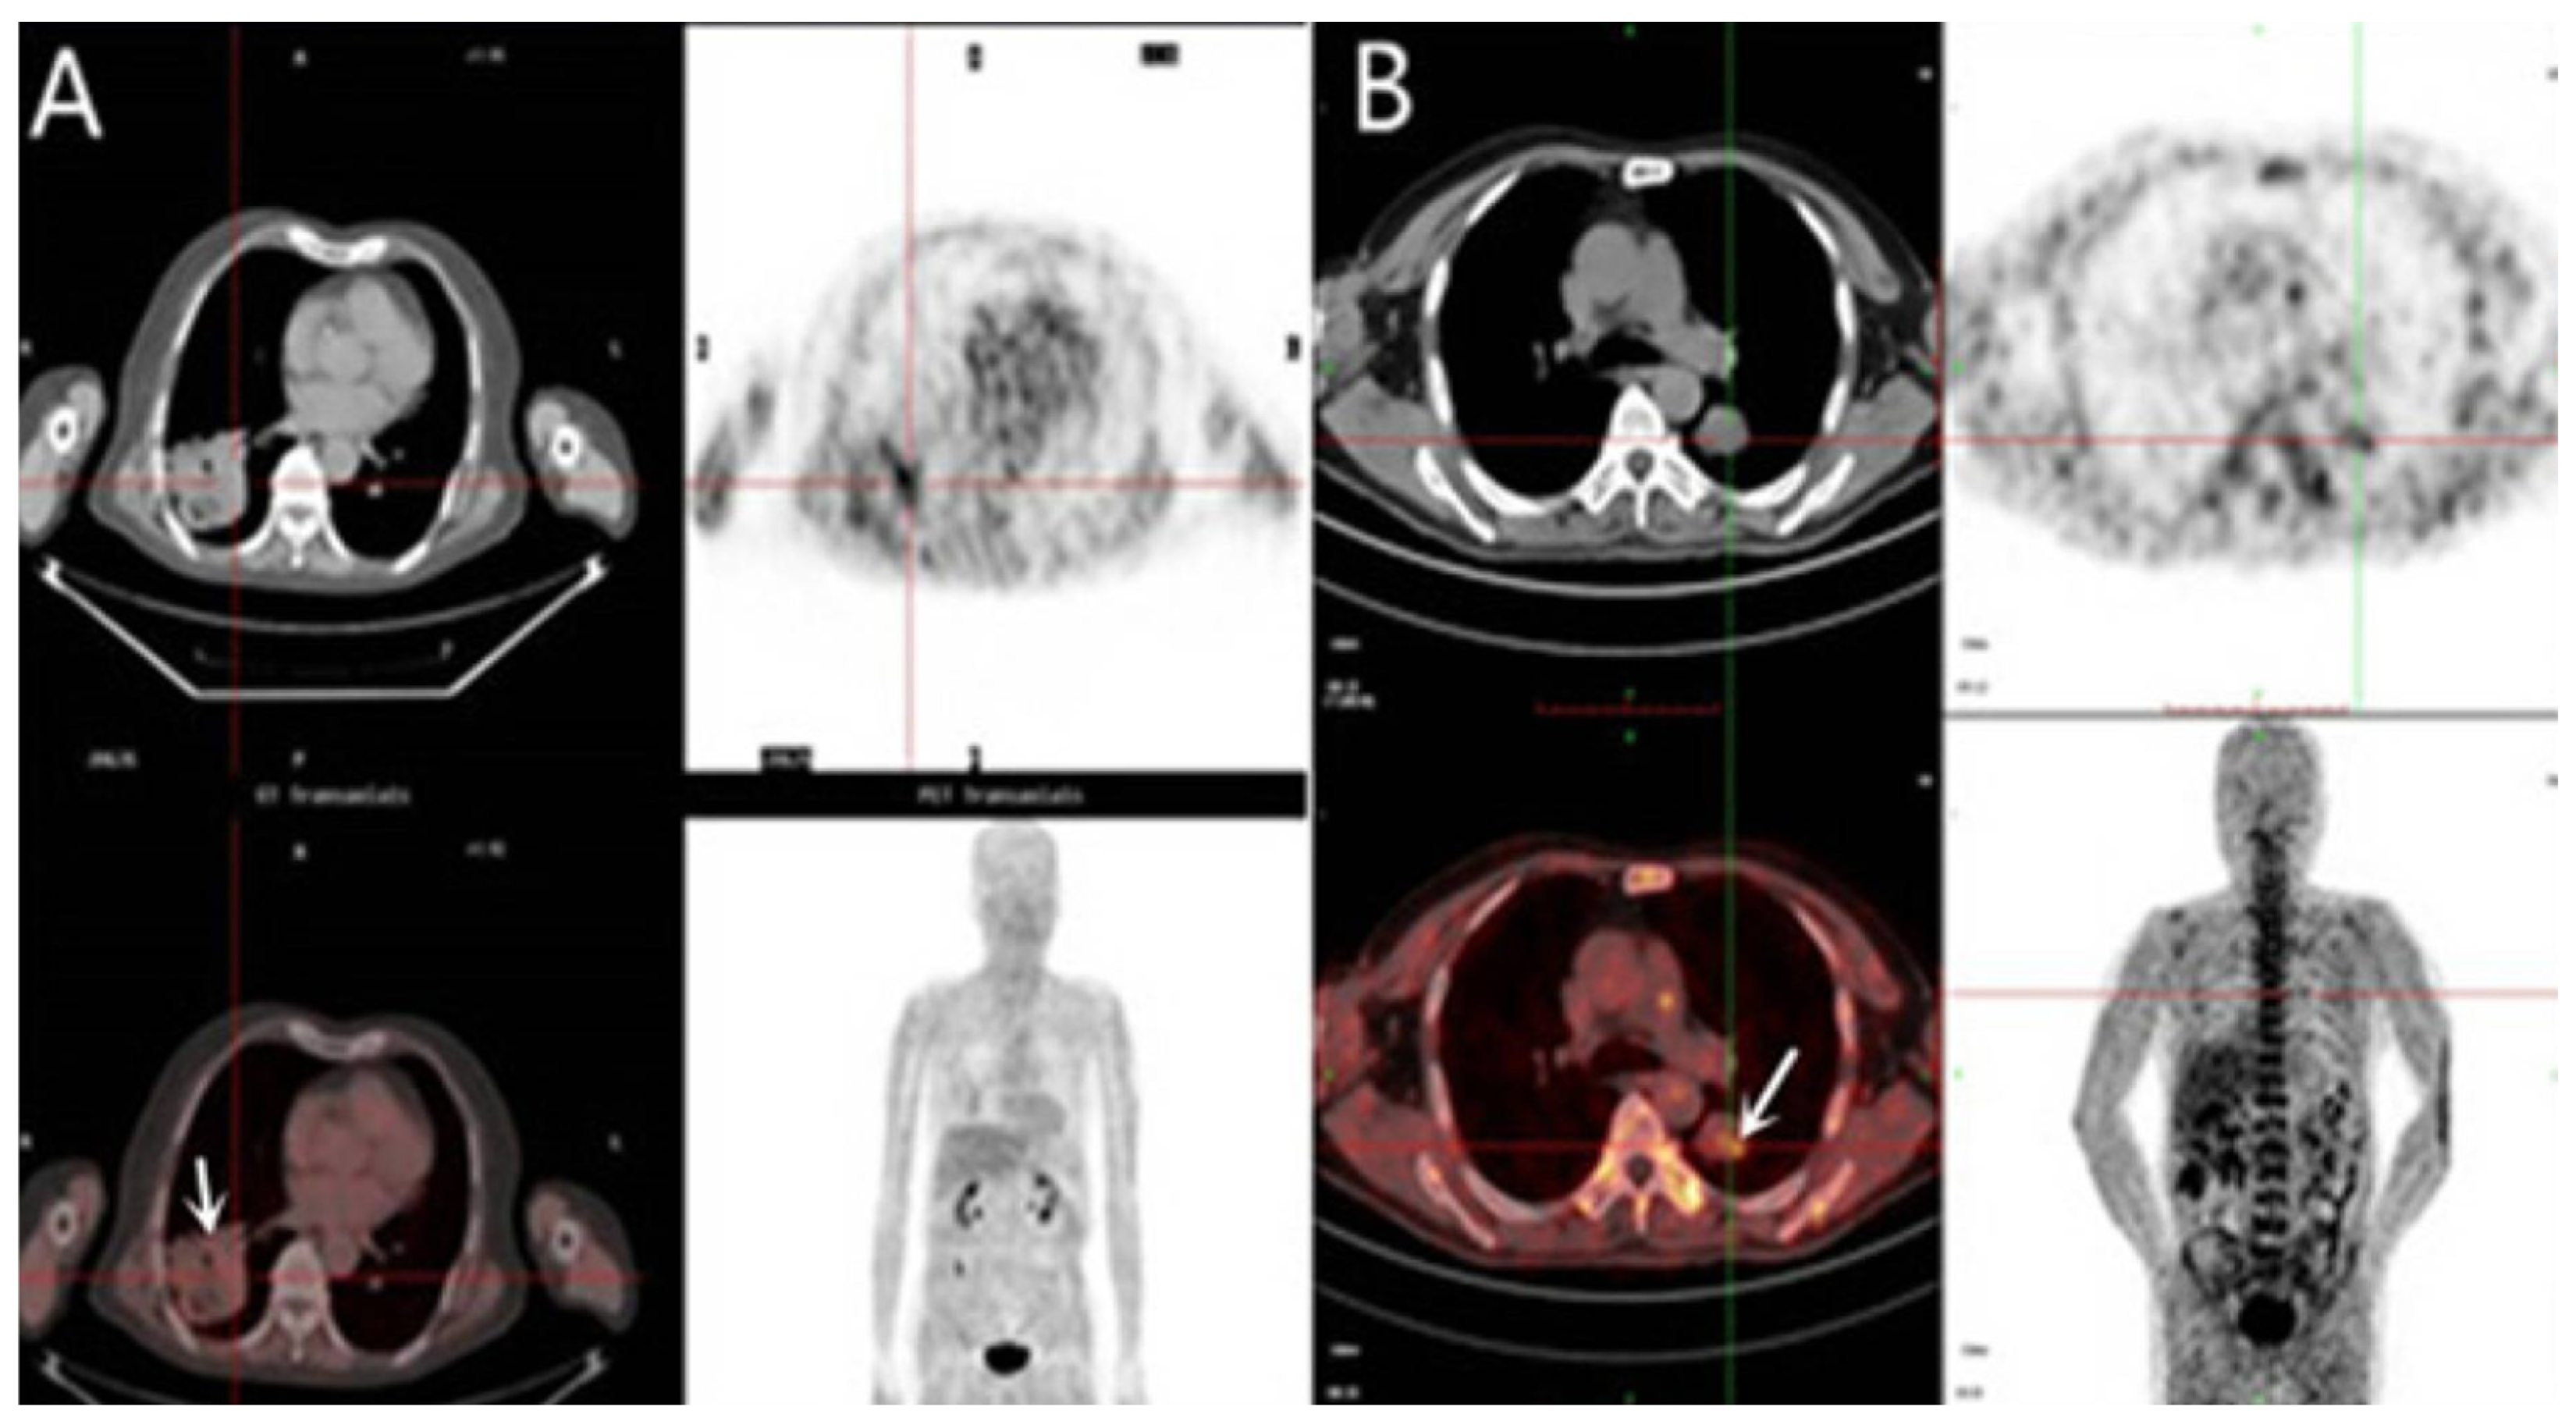

3.3. Hypoxia PET Imaging

3.3.1. 18F-Fluromisonidazole (18F-FMISO)

3.3.3. 18F-FDG